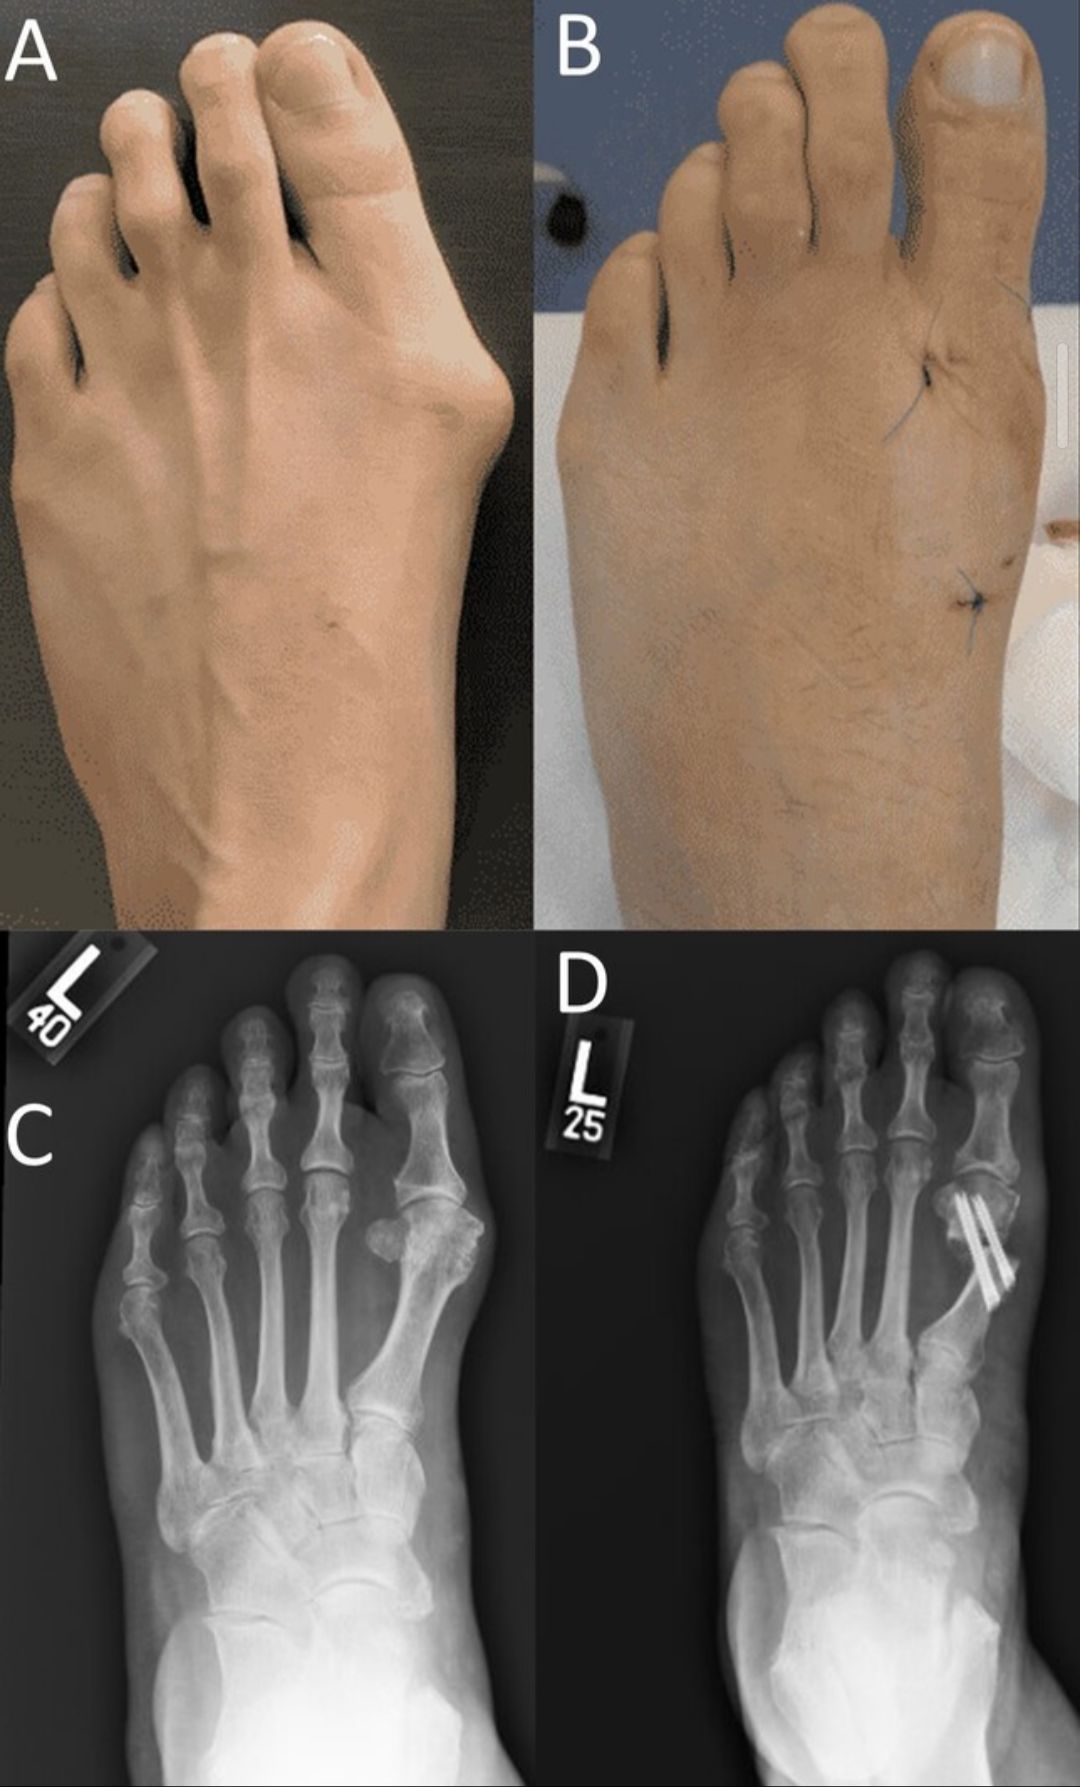

Juanetes

El juanete es una deformidad del dedo gordo del pie que puede generar dolor, inflamación, dificultad para caminar y problemas para usar calzado. Suelen progresar con el tiempo si no se evalúan adecuadamente. Se realiza una evaluación clínica y radiográfica completa para definir el tratamiento más adecuado en cada caso, según la deformidad, los síntomas y la actividad del paciente. El abordaje puede incluir opciones conservadoras o corrección quirúrgica cuando está indicada, con el objetivo de aliviar el dolor y mejorar la función del pie.